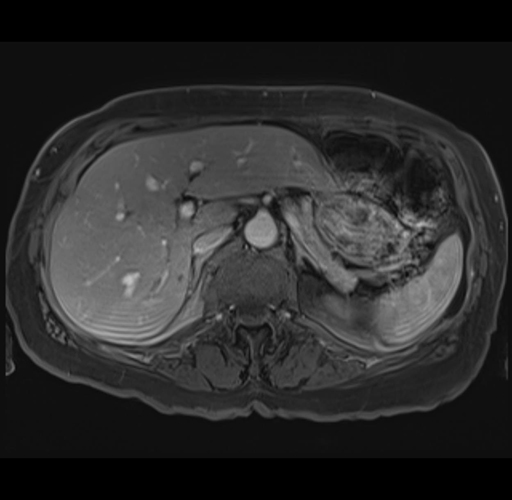

MRI T1

Imaging analysis

Based on your CT findings, which issue(s) would give reason for "planned slowing down moment(s)" in this case?

Considering a standard right hepatectomy procedure, what step(s) of the operation would you do differently in this case?